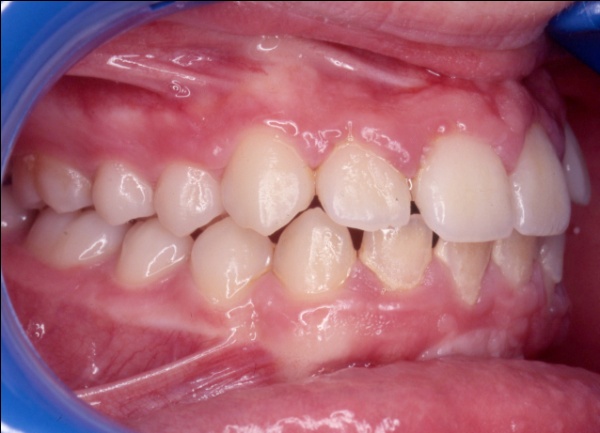

Ce cas illustre parfaitement que l’orthodontie ne peut pas se résumer à un simple alignement des dents. Ici, l’exclusion de la canine supérieure gauche (23) pouvait faire croire à un manque de place dû à un excès de volume dentaire. En réalité, un diagnostic précis a révélé deux causes : une endomaxillie (palais trop étroit) et une avancée anormale de l’hémiarcade gauche, qui empiétait sur l’espace de la canine. Le traitement a consisté à élargir le maxillaire par disjonction, puis à réaligner les dents sans extraction, en restaurant l’harmonie occlusale.

1 - Arcades avant/après

Le traitement a été conservateur, sans extraction, grâce à une thérapeutique de gain d’espace adaptée. L’arcade a retrouvé sa largeur, son équilibre et son esthétique, par la restitution d’une architecture osseuse et dentaire cohérente. L’occlusion est désormais fonctionnelle, stable et conforme aux rapports naturels entre les deux arcades.